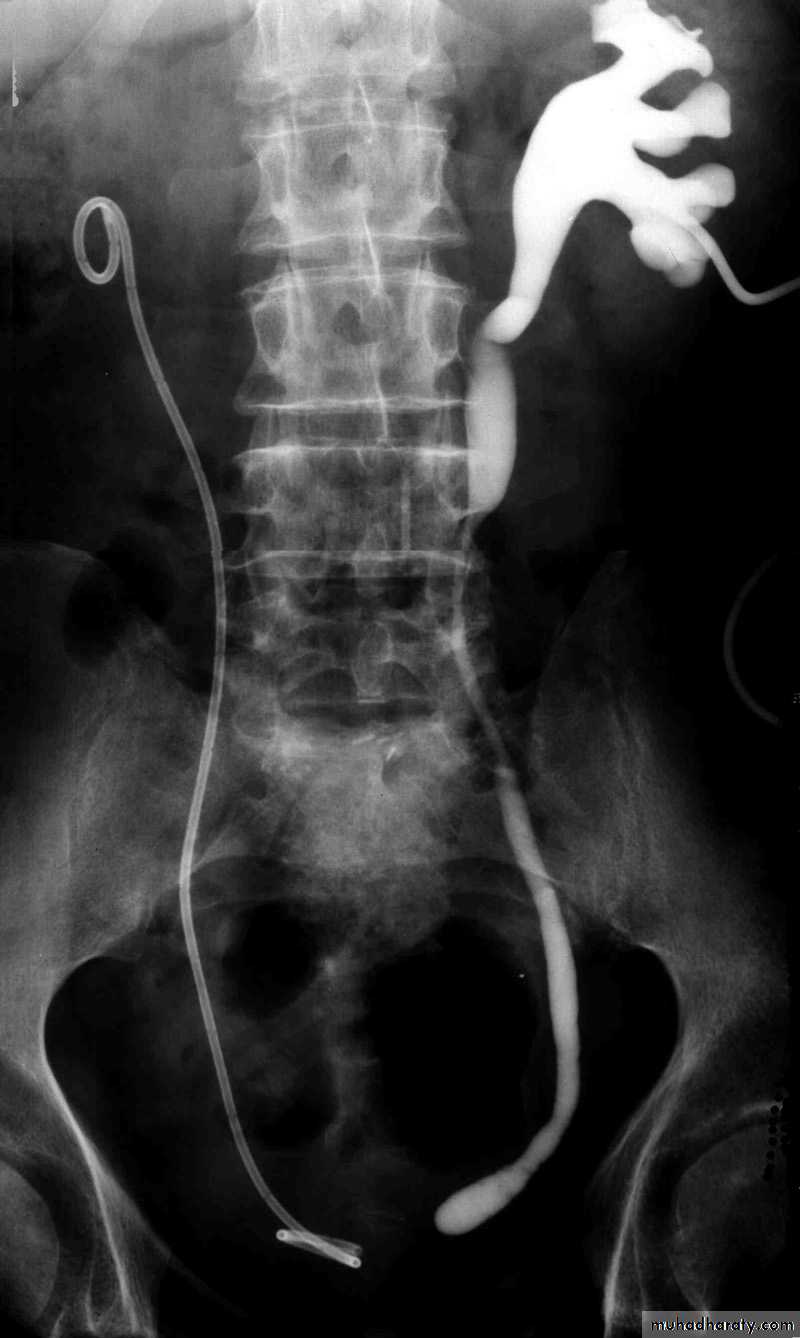

Postcaval (Retrocaval) ureter (Preureteral Vena Cava )

Congenital  anomalies of the upper urinary tract

The right ureter pass behind the inferior vena cava

This might causes obstruction

Vascular abnormality

Incidence: about 1 in 1500

Although it is congenital, most patients present at 3rd or 4th decade.

Diagnosis: IVU

Treatment:

surgical correction involves ureteral division, with relocation and ureteroureteral or ureteropelvic reanastomosis,

usually with excision or bypass of the retrocaval segment, which can

be aperistaltic